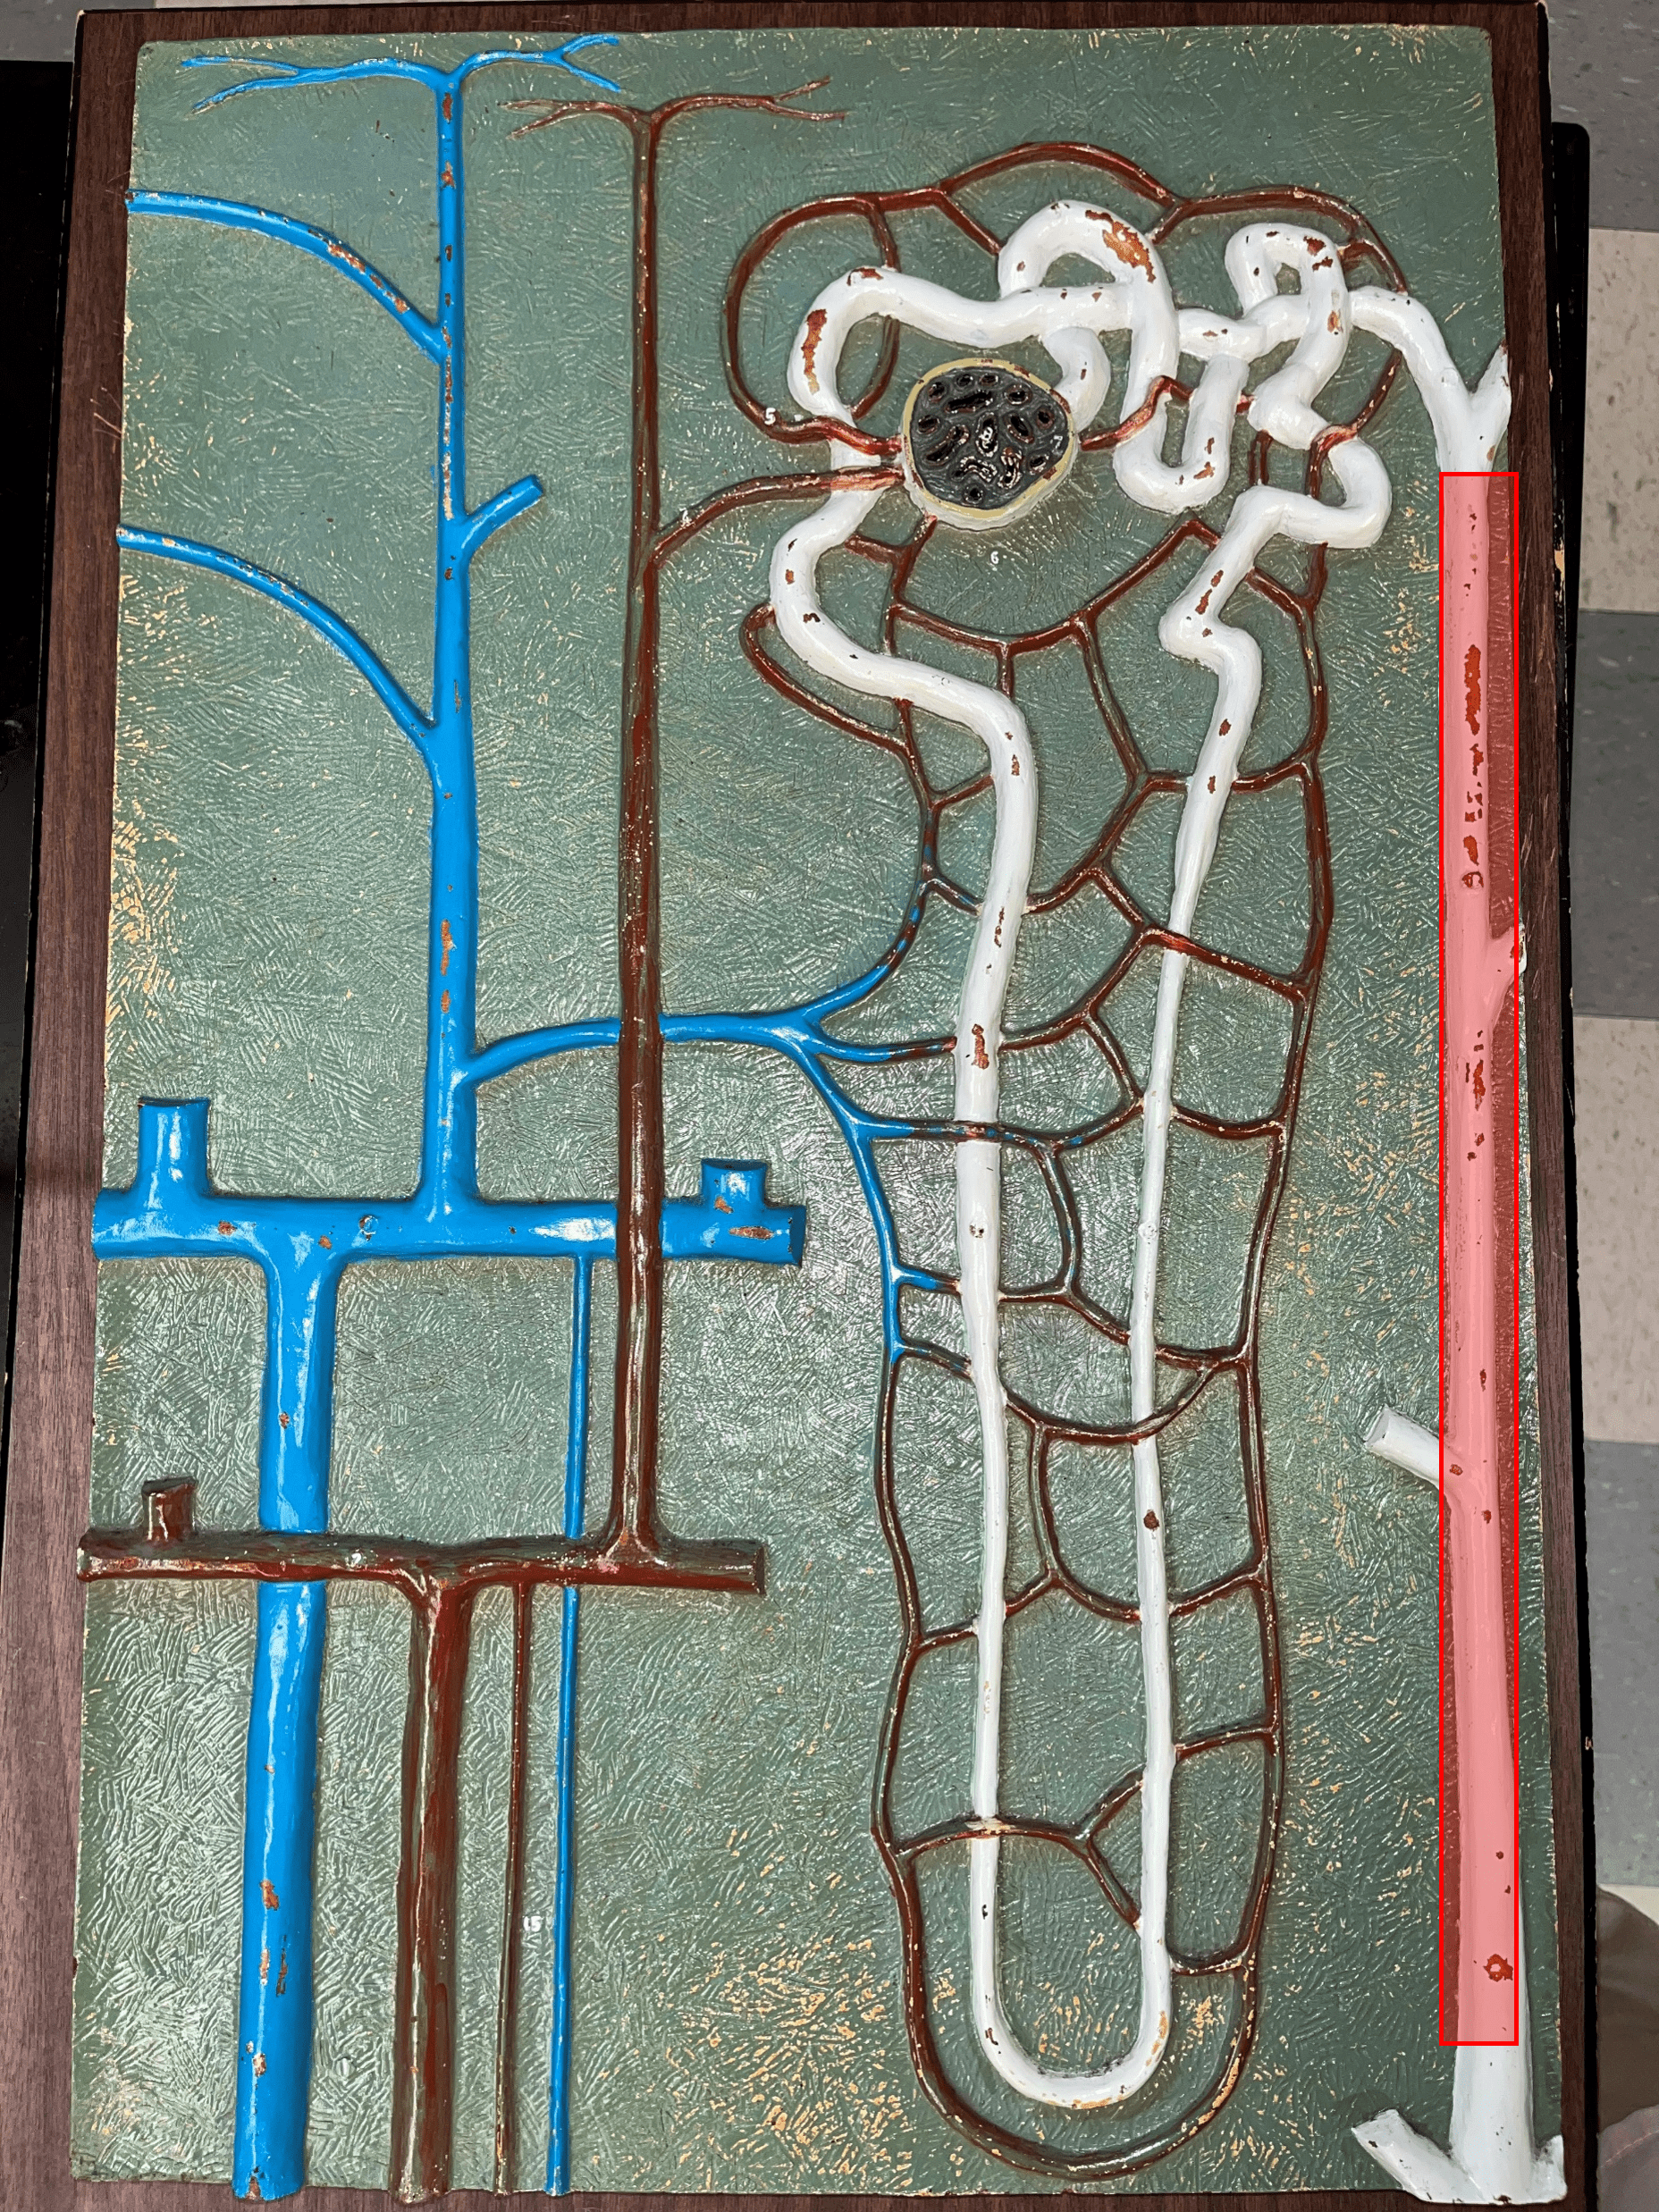

nephron

• The functional subunit of the kidney.

• Site of urine formation and renal function.

• Composed of a renal corpuscle and a renal tubule.

• Site of urine formation and renal function.

• Composed of a renal corpuscle and a renal tubule.

40

New cards

renal corpuscle

• Part of a nephron.

• Filters blood.

• Composed of a glomerulus enclosed within a glomerular capsule.

• Filters blood.

• Composed of a glomerulus enclosed within a glomerular capsule.

41

renal tubule

• Slide histology of the nephron.

• Part of a nephron.

• Modifies glomerular filtrate by reabsorption and secretion of water and ions.

• Divided into the proximal convoluted tubule, loop of Henle, and distal convoluted tubule.

• Part of a nephron.

• Modifies glomerular filtrate by reabsorption and secretion of water and ions.

• Divided into the proximal convoluted tubule, loop of Henle, and distal convoluted tubule.

48

proximal convoluted tubule

• The first part of a renal tubule.

• Primary site of water and solute reabsorption.

• Begins immediately after the renal corpuscle.

• Abbreviated PCT.

• Primary site of water and solute reabsorption.

• Begins immediately after the renal corpuscle.

• Abbreviated PCT.

49

collecting duct

• The convergence of several distal convoluted tubules.

• Descends through the renal pyramid.

• Merges with others to form larger papillary ducts that drain into the minor calyces.

• Abbreviated CD.

• Descends through the renal pyramid.

• Merges with others to form larger papillary ducts that drain into the minor calyces.

• Abbreviated CD.

53

afferent arteriole

• Branches of an interlobular artery.

• Supplies the glomerulus of a nephron for blood filtration.

• Supplies the glomerulus of a nephron for blood filtration.

efferent arteriole

Vessel carrying blood away from the glomerulus to the peritubular capillaries.

peritubular capillaries

• Branches of an efferent arteriole.

• Supplies the adjacent renal tubules in the renal cortex.

• Supplies the adjacent renal tubules in the renal cortex.

vasa recta

• Branches of an efferent arteriole.

• Supplies the loops of Henle in the renal medulla.

• Supplies the loops of Henle in the renal medulla.